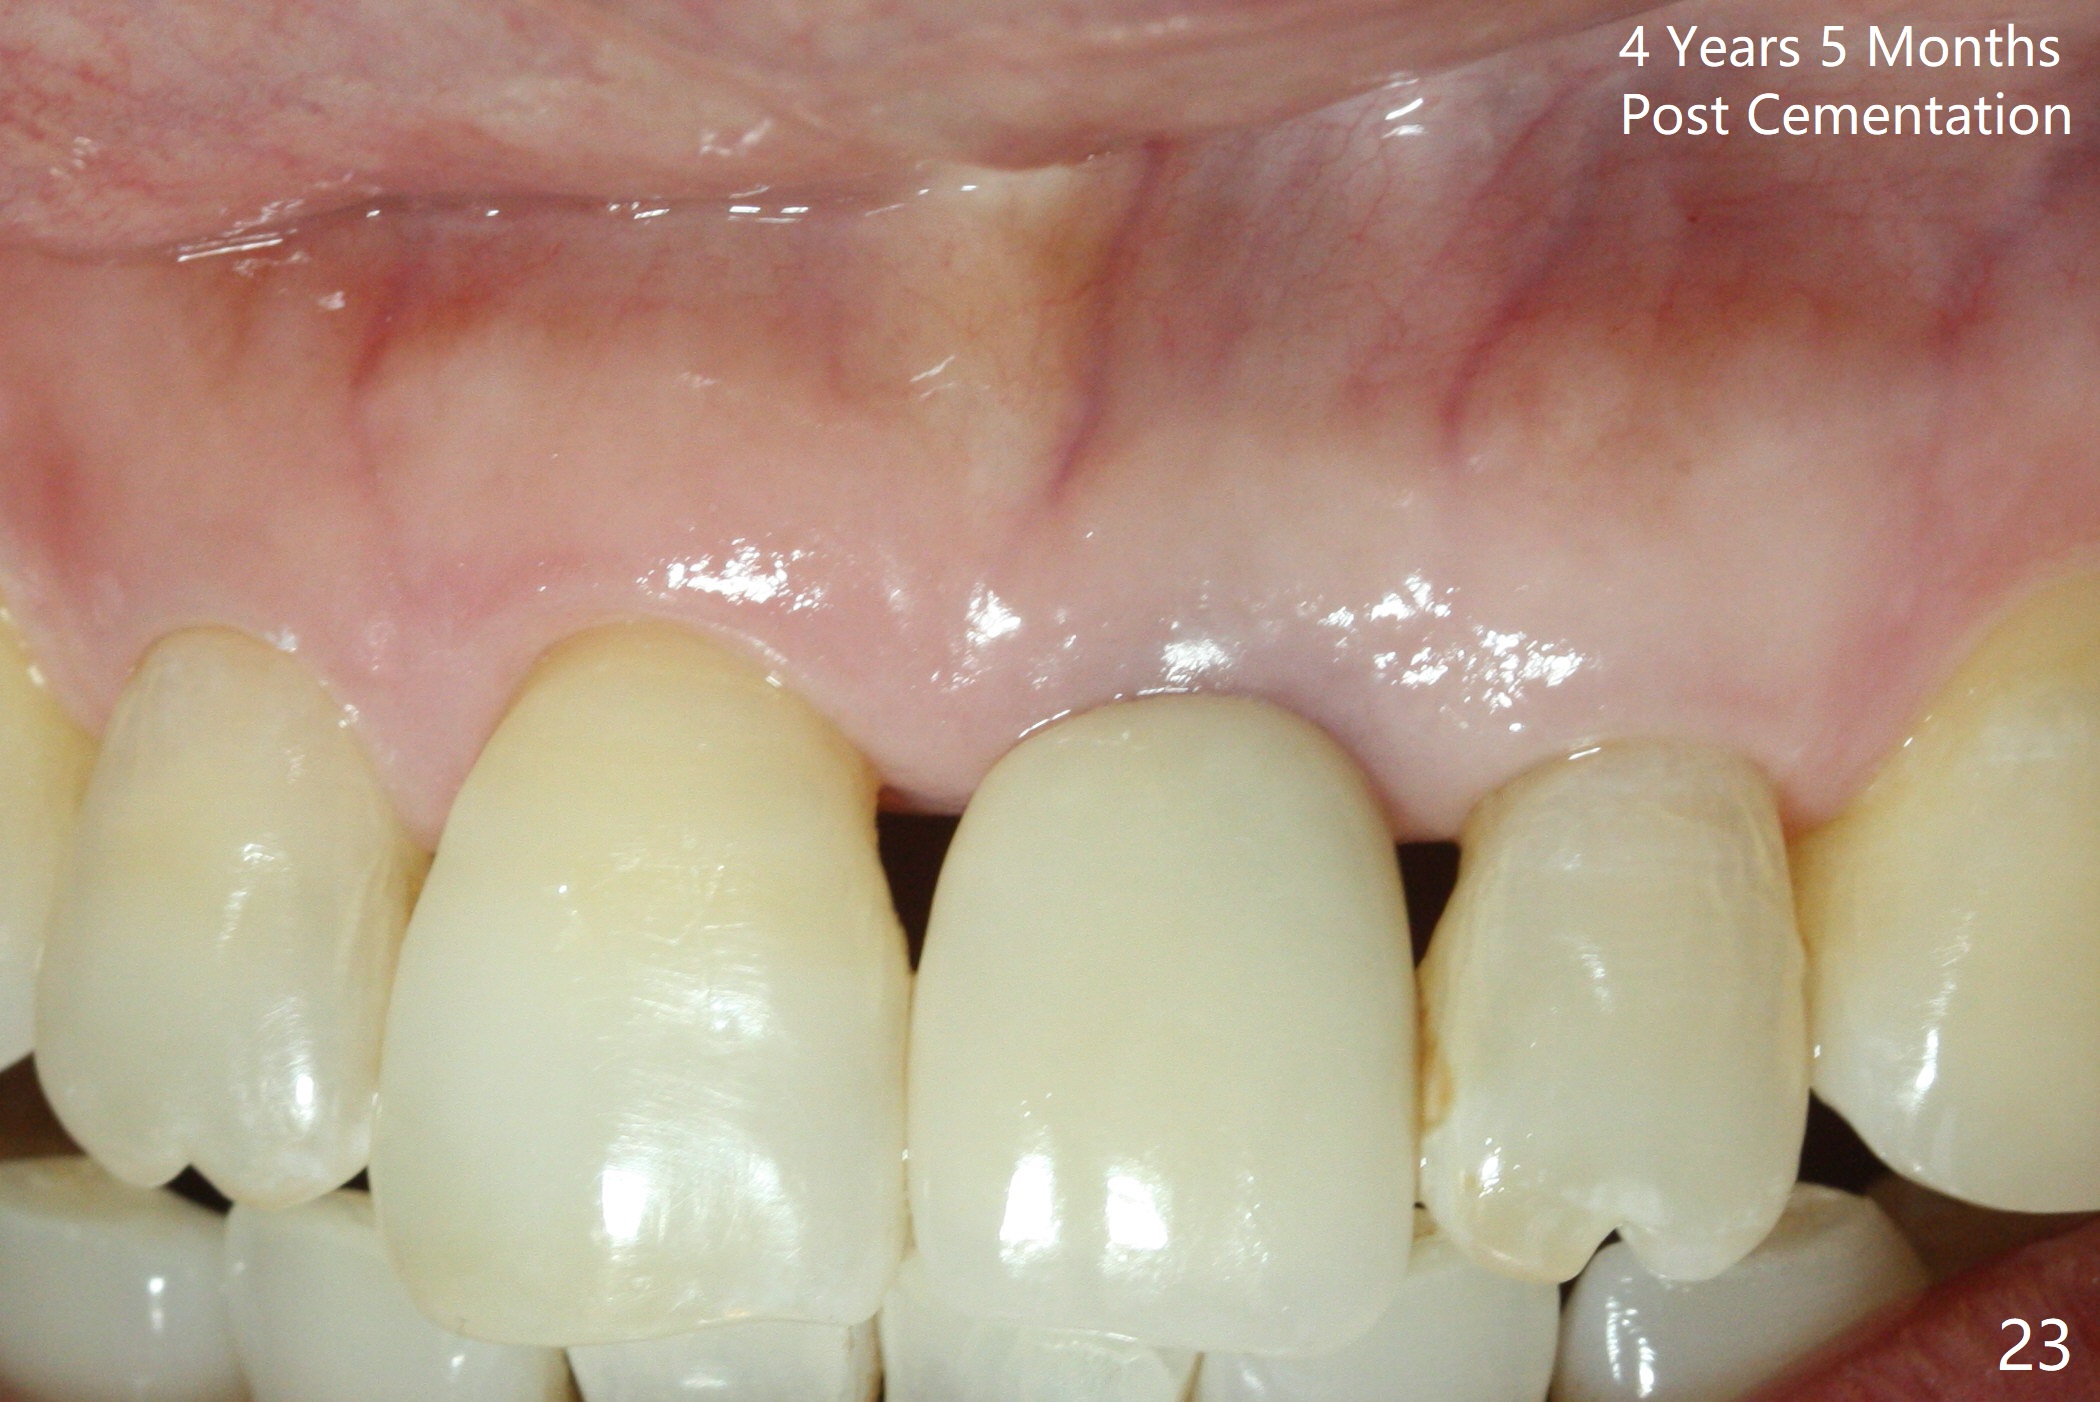

A 60-year-old lady had an abscess mesial to #9 six years ago (Fig.1,2 <), treated as a perio lesion by laser (Fig.3) and osseous surgery without bone graft (Fig.6, followed by CT exam revealing semi-circumferential bone loss (Fig.4,5). When the perio treatment failed, attention was paid to endo aspect (Fig.7-9). In fact the pulp was found to be vital when access to root canal therapy was made. As expected, the treatment failed again. The palatal fistula persisted. The infection was suspected to be a source of remote immediate implant site (#30). The tooth #9 was extracted. It appears that there is a semilunar crack line in the linguomesial root (Fig.12). When the socket healed 2 weeks post extraction (Fig.10), the #30 buccal defect was debrided with bone graft. There was no bone resorption 4 weeks post extraction (Fig.11); a 4.5x17 mm implant was placed (Fig.13-15). An immediate provisional was fabricated (Fig.16-18). Fig.19,20 were taken 3 months post implantation and 7 months post cementation, respectively. Dense bone forms around the implant coronally 4 years 5 months post cementation (Fig.21), while the gingiva is healthy palatally (Fig.22) and buccally (Fig.23).